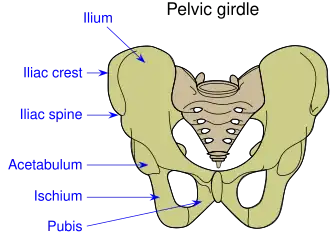

Overview of Ilium as largest region of the pelvis. | |

Pelvic girdle

Pelvic girdle -